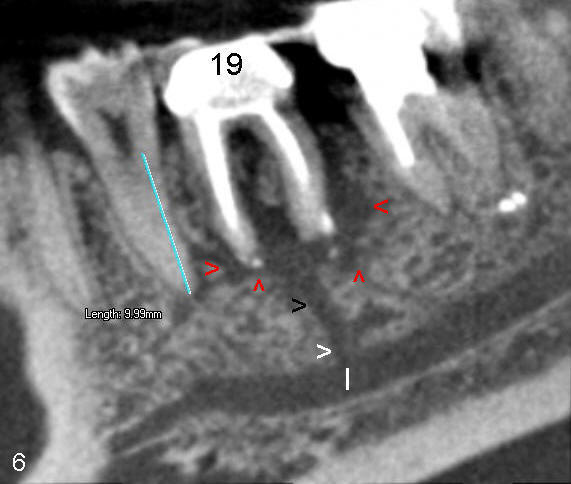

Fig.6  If PARL disappears whereas the abnormal communication does not, the hypothesis of abnormal branch of the inferior alveolar nerve is established.  This proves to be bad news for implantologist.  He has less bone height (~ 6 mm in this case) to place an implant in the first molar area, back to original article